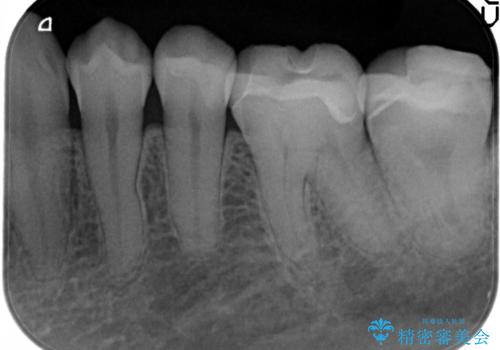

- 定期検診にて虫歯が見つかり、セラミックインレーに治療を行っております。

e-max プレスインレーにて修復治療を行っているため適合性及び審美性の高い治療を行うことができます